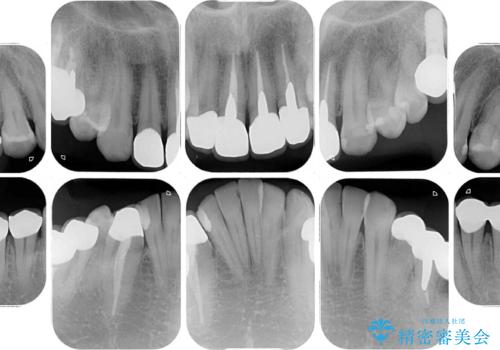

目立つ金属をすべてセラミックに 全顎的メタルフリー治療

- 黄ばんだ前歯や目立つ奥歯の銀歯をきれいにしたいとのことで来院された患者様です。

欠損している歯や、割れてしまって抜歯の必要な歯などがあり、咬合力が強いため欠損部はインプラント補綴を前提に治療を行うこととしました。

しかしながら、左下の抜歯部位は骨欠損が著しく大きく、多大な垂直的骨造成を要するため、3歯を支台としたブリッジによる補綴治療とし、右下のみをインプラント補綴としました。

小さい修復物の銀歯が装着されている歯はセラミックインレーにて、その他はオールセラミッククラウンにて補綴治療を進めることとしました。